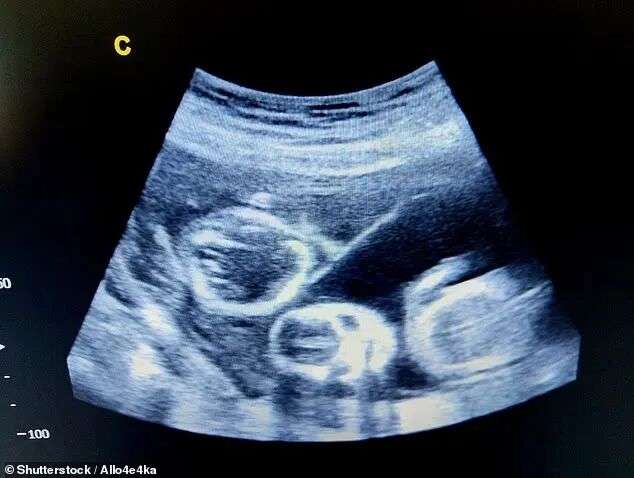

直到第11周去产检时,医生注意到两个胎儿不像同卵双胞胎,等16周产检时更加确认了这一点,因为两个胎儿的性别不同。

单个胚胎如果分裂,只会产生基因完全一致的同卵双胞胎,两个孩子性别不同,就证明他们并非来自同一胚胎,其中一个只能是Courteney的。

(一对毫无血缘关系的“双胞胎”)

现在Courteney怀孕刚满22周,预产期在12月。那时,她将生出一对极为罕见的异父异母“双胞胎”,在她看来,两个孩子更像“室友”关系。